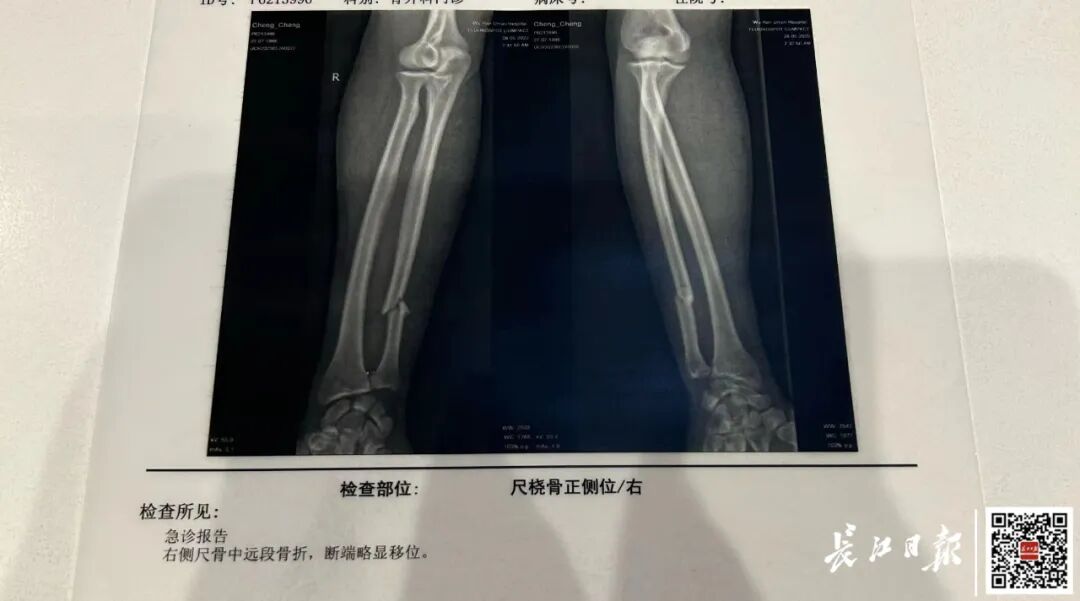

医生诊断

其右侧尺骨骨折

全身多处皮肤挫伤

目前,仍在治疗中

程成右臂骨折。记者谢冰林 摄